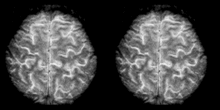

Cognitive neuroscience aims to reduce cognition to its neural basis using new technologies such as fMRI, repetitive transcranial magnetic stimulation (rTMS) and Magnetoencephalography (MEG) as well as older methods such as Positron emission tomography (PET) and Electroencephalography (EEG) studies. Due to the correlational designs used in fMRI, many scientists have coined this up and coming field as the new phrenology in the sense that techniques such as fMRI rely heavily on complex statistics.[17] Type 1 errors can lead scientists to draw premature and incorrect causal relationships if improper designs are used.[18]

Functional magnetic resonance imaging (fMRI) has intriguing implications for the study of memory in humans, however it can also be used in animal models. fMRI can be used to assess brain functionality in monkeys in the context of a variety of behavioral tasks.[26] Structural MRI can be used to examine the extent and location of brain lesions, so that behavioral abnormalities observed can be directly linked to specific brain structures.[27] High-resolution fMRI can help locate and assess the functionality of large neural networks so that these regions can be further studied using more traditional electrophysiological recording devices.[26]